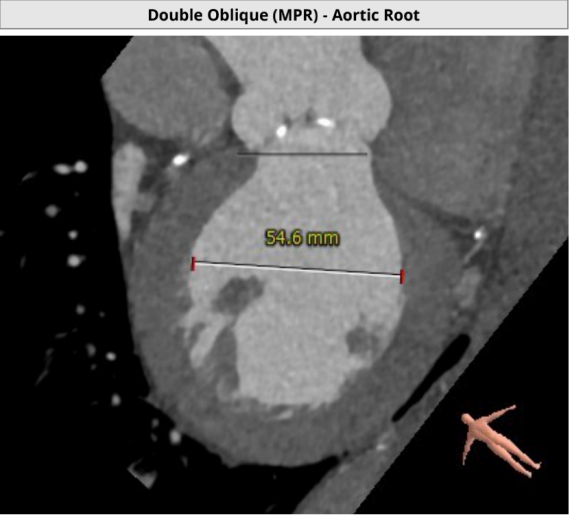

患者主动脉根部、冠状动脉、主动脉增强CT扫描,通过专业评估软件分析提示该患者主动脉瓣为功能型二叶瓣、中度钙化,左右冠窦可见融合、瓦氏窦结构较大,左右冠开口高度尚可,升主动脉最宽处约42.9mm,左室明显扩大。主动脉瓣环平均径约26.3mm,流出道平均径约27.5mm,STJ平均径约34.3mm,双侧股动脉直径均大于6mm。冠脉见钙化灶,钙化积分总和为1590.2;冠脉CTA提示:“左主干、三支冠状动脉粥样硬化改变,局部管腔可见40~60%狭窄”。

升主61.4mm处增宽:42.9mm